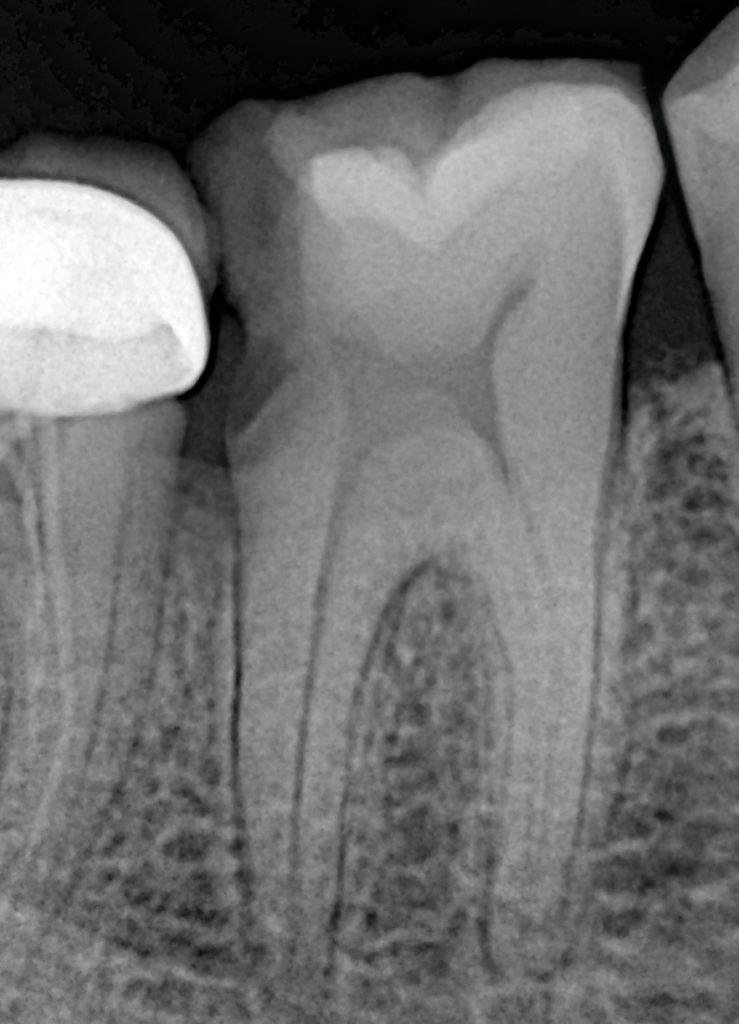

- Tooth showed irreversible pulpitis with deep distal decay and no ferrule.

- Pre-operative radiographs confirmed canal anatomy.

2. Caries Removal & Access

- Caries removed conservatively, ensuring all affected dentin was cleared while preserving pericervical dentin.

- Four clean canal orifices identified.

4. Deep Margin Elevation (DME) – 2-Step Technique

Step 1:

- Matrix adaptation and gentle tissue displacement achieved.

- First increment placed using a high-filled nanohybrid composite to lift the margin away from the sulcus.

Step 2:

- After the first layer cured, the final enamel-level elevation was performed using a more enamel-like composite.

- This ensured a clean, dry, supragingival margin for the final restoration.